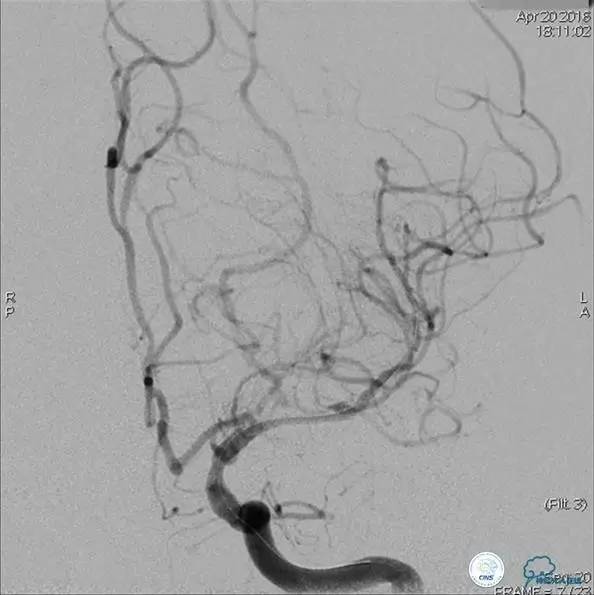

患者:49岁女性,脑梗死30天。

左侧颈内动脉末端闭塞,末端圆钝且有一定成角,开通难度较大,多次尝试导丝才成功穿过闭塞段。

开通效果很满意,术后症状明显恢复。